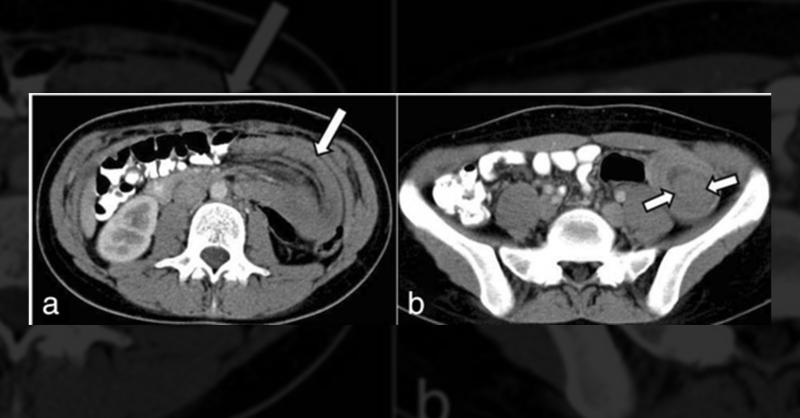

A 19-year-old woman presented to the emergency department with recurrent non-specific cramping and intermittent left lateral abdominal pain lasting four days. Accompanied by nausea and vomiting, she had previously been admitted twice with symptoms of incomplete obstructive ileus, featuring partial gas and feces retention. The patient had no signifi